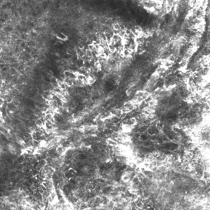

Confocal microscopy images

This is a collision tumour in which a melanoma in situ and a solar lentigo are both occurring in the same lesion.

These two diagnoses are different and separate, and this case demonstrates that if a partial sample biopsy is taken, you may miss the other diagnosis.